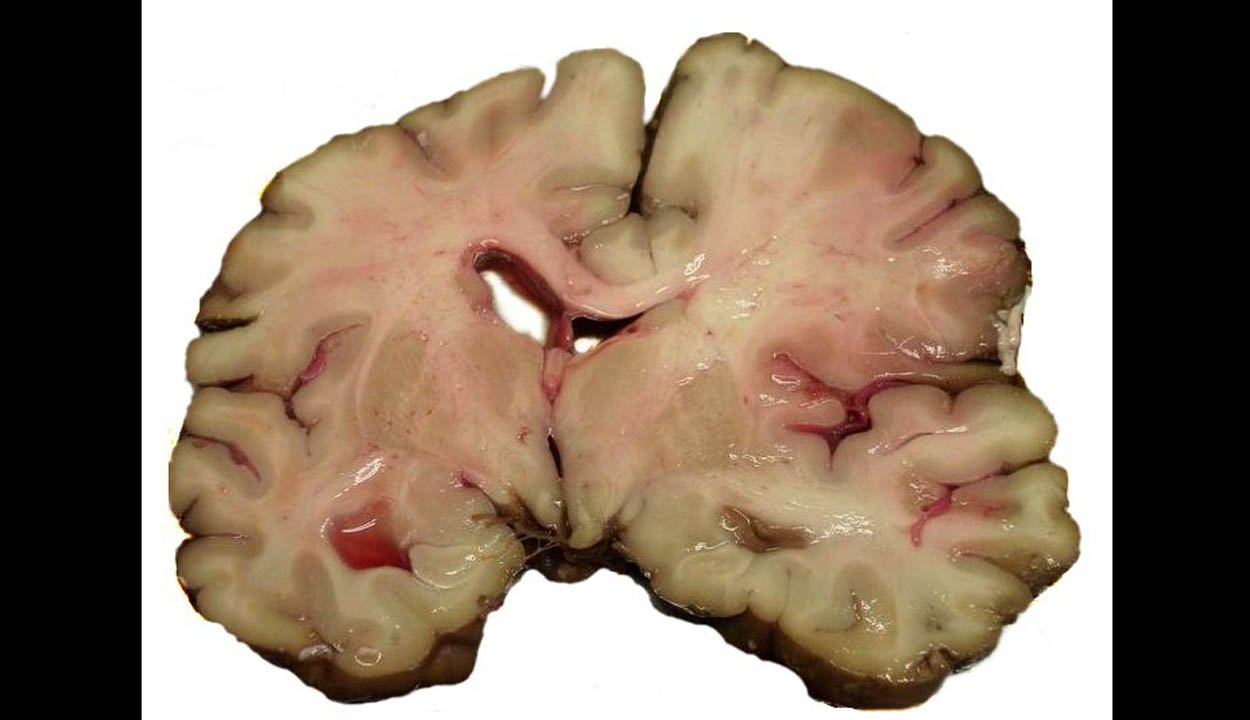

A statisztika ellentmondásos, mert a súlyosabb következmények megelőzését célzó érrendszeri gyógykezelések számának emelkedése azt is jelenti, egyre többen korán felismerik az első tüneteket, és idejében jelentkeznek orvosnál. Idén a szakorvosok 63 páciens esetében tudták elvégezni a trombolízis néven ismert beavatkozást. Tavaly egész évben 52 trombolízis volt a sepsiszentgyörgyi kórházban.

Az agyvérzéssel, stroke tüneteivel kórházba került személyek száma viszont mindkét évben ennél sokkal nagyobb, ami azt is jelenti, nem minden esetben lehet alkalmazni a trombolízist. A szakorvosok felhívják a figyelmet arra, hogy az életmentő beavatkozások sikerének, illetve az agyi és egyéb szervi károsodások elkerülésének záloga az idejében történő felismerés, az első tünetek észlelése utáni minél gyorsabb orvosi beavatkozás.

Az agyérbalesetek gyógyításában és megelőzésében végzett eredményes munkájának elismeréseként a sepsiszentgyörgyi kórház szakosztálya megkapta az ESO Angels Awards orvosi szervezet és az Európai Stroke Társaság Platinum díját, ez a tavalyi Gold (Arany) kitüntetésnél magasabb fokozat. <<